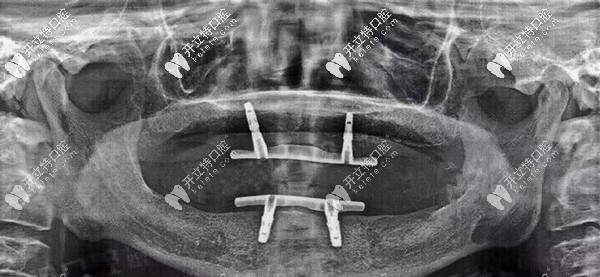

陳叔叔口腔檢查情況

▲陳叔叔口腔檢查情況